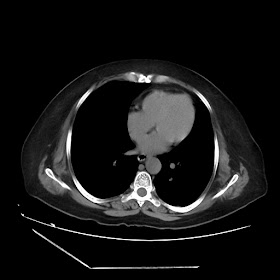

A 70 years old woman with Obstractive jaundice & palpable GB

Latest Radiological images: